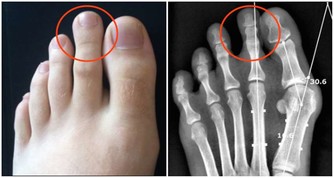

當時因為幾乎無法彎腰,或勉強彎下後就很難挺直的腰部問題,我去了台北某大醫院的骨科求診。

那位醫生從病歷表看到我的年齡後,不僅X光片沒用心看,連聽也沒聽我講完,

就直接對我說:「這是上了年紀,退化了,我開個藥……」

我聽了非常震驚,這實在是太「不可思議」了,怎麼會遇到這樣的醫生,居然對我輕易地下了審判。

但是我實在是因為太不舒服又太不方便了,隔天又到另一家醫院掛號。

這回,我找的是復健科。

而當醫生看了X光片後,一開口卻是:「你怎麼還不趕快辦理住院、開刀!」

我只是直覺地回說:「我不想開刀!」

醫生接著說:「那就長年復健!」

我心想別無他途了,所以只好接受該醫院的拉腰復健,

但做了三次後沒有改善,於是就放棄了在醫院的復健之路。